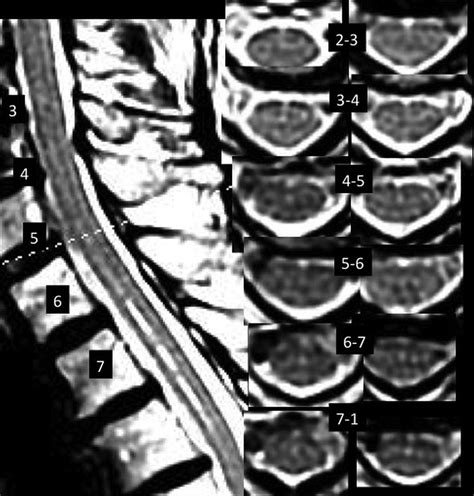

• Diagnostic Imaging: Magnetic resonance imaging (MRI) and computed tomography (CT) scans can be used to visualize the anterior fissure and assess its integrity. These imaging techniques are essential for diagnosing spinal cord injuries and neurological disorders.

• Imaging Techniques: MRI and CT scans are essential for visualizing the spinal cord and the anterior fissure. These imaging techniques can help identify structural abnormalities, such as tumors or fractures, and assess the integrity of the anterior spinal artery.